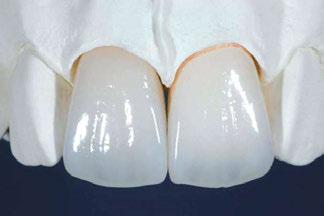

Ciencia y clínica Rehabilitación 100% digital: desde la planificación a la carga

Presentamos el tratamiento rehabilitador de una paciente, realizado íntegramente en una sesión. Para este caso se ha utilizado un protocolo quirúrgico digital y guiado mediante la Plataforma de Planificación Bego Guide. Asimismo, se ha diseñado digitalmente una prótesis de carga inmediata atornillada e impresa con resina Bego VarseoSmile TriniQ®. Por lo tanto, se trata de un caso cuyo tratamiento precisa diferentes fases, pero efectuadas, todas ellas, el mismo día. De forma sencilla y cómoda para la paciente y el odontólogo, se ha obtenido una rehabilitación fija, funcional y estética. Palabras clave: Cirugía guiada, implantología oral guiada, cirugía sin colgajo, férula quirúrgica, rehabilitación fija maxilar, impresión digital, escáner intraoral, implantes dentales.

Ejecución técnica protésica

aproximadamente una hora y media. Usamos resina Bego VarseoSmile TriniQ® para puentes definitivos. Aunque en este caso la vamos a usar para confeccionar unas prótesis fijas atornilladas provisionales de larga duración, dado al aumento de dimensión vertical que vamos a realizar a la paciente, de esta forma obtendremos una neuroprogramación de la ATM reinstaurando una Dimensión Vertical apropiada y mejorando la estética facial de la paciente. Excluimos de la carga aquellos implantes que no obtuvieron una estabilidad primaria superior a 35 N/ cm2. El material permite la realización de una carga inmediata en material definitivo en puentes (Figuras 31 a 38).